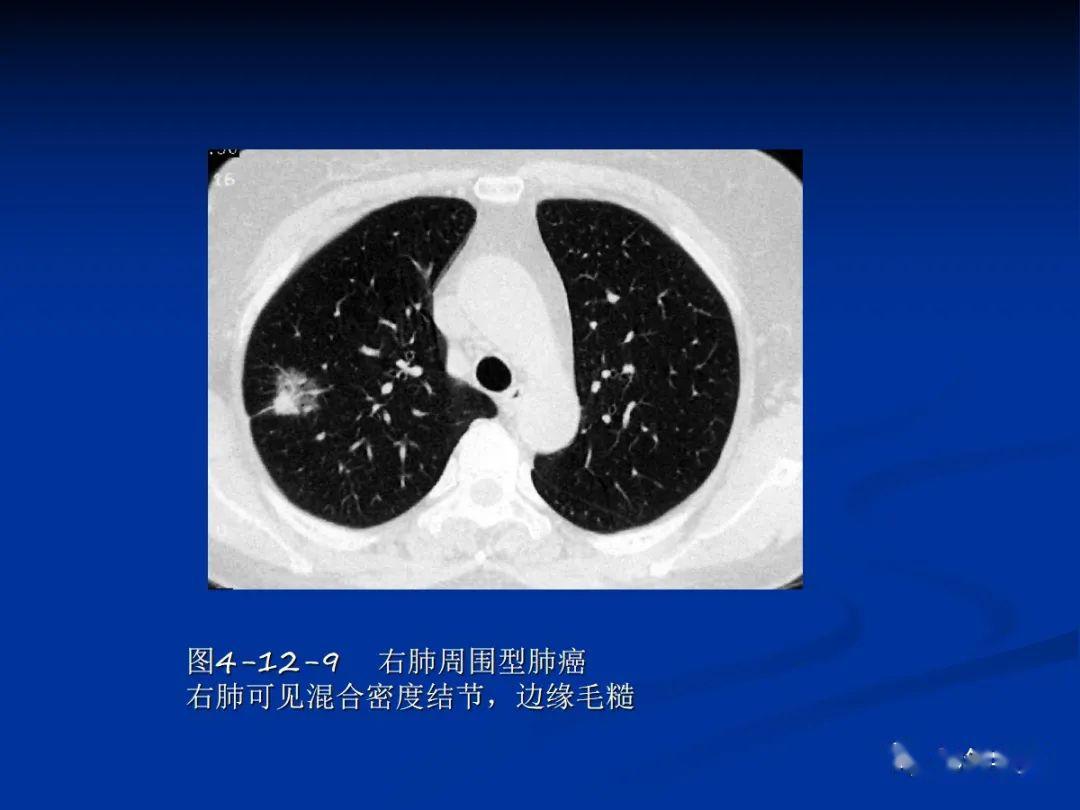

医学影像学第七版 肺肿瘤ppt

肺肿瘤影像学汇总

肺部疑难肿瘤病变的影像学诊断ppt